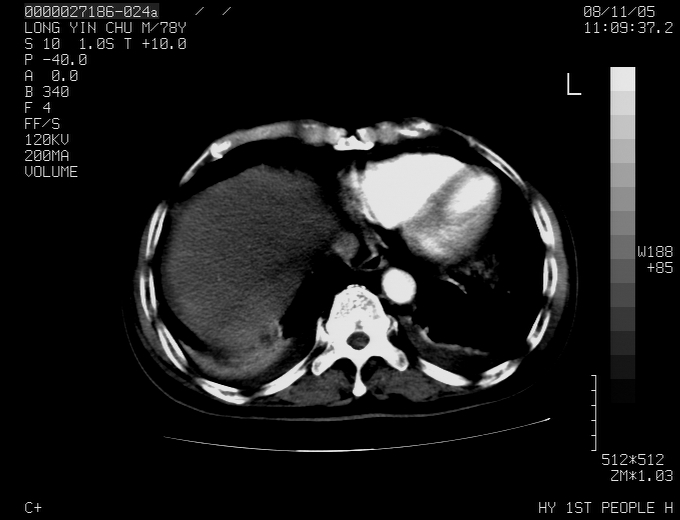

标题: CT16532:M78Y,肝脏病变,请会诊

腹胀,腹痛就诊,男性,78岁,外院b超未见异常。

肝ca,脾肾转移

支持脾肾转移瘤,双侧胸腔积液。

考虑弥漫性肝癌并脾及双肾转移.双侧胸水.